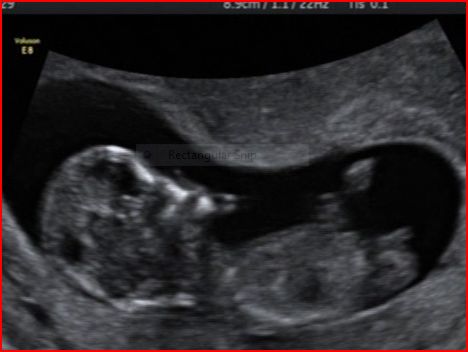

I have attached a copy of some stills from the dvd we have been given if anyone fancies a guess at the nub - first proper shot of baby is (by the us clock) ironically at 12:12 on the 12.12.2012.

Attachment 7238

Baby was 12+1 at the time of shots (hopefully, if everthing is ok and i haven't m/c'd before then from the cvs, i will post another one that i get from my 13 week nt scan on tuesday)